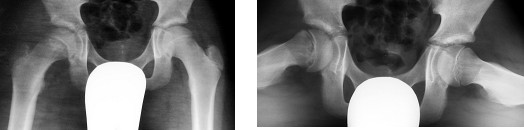

Dziecko w wieku 5 lat i 9 miesięcy zgłosiło się do ortopedy z powodu dolegliwości bólowych lewego stawu kolanowego i okresowych dolegliwości bólowych lewego stawu biodrowego. W badaniu klinicznym stwierdzono niewielkie ograniczenie ruchów odwodzenia w stawie biodrowym i rotacji do wewnątrz. Podczas chodzenia dziecko wyraźnie utyka na kończynę dolną lewą. Objaw Trendelenburga jest dodatni. Wykonany w dniu badania radiogram stawów biodrowych zamieszczony jest poniżej. Obraz kliniczny i radiologiczny przemawia za:

Pytanie 105